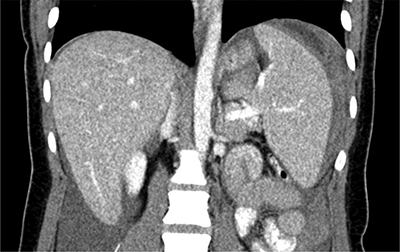

Figure 3

Contrast-enhanced abdominal CT shows a haemoperitoneum and splenomegaly. A hyperdense, perisplenic suggests an acute perisplenic haematoma.